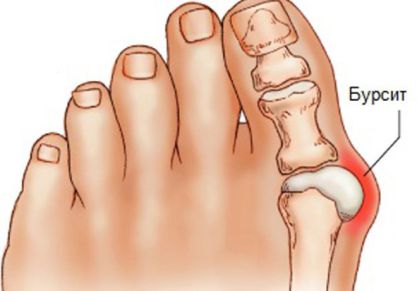

• Бурсит. Он считается достаточно неприятным заболеванием, которое характеризуется появлением воспалительного процесса в суставной сумке. При этом внутри полости сочленения накапливается экссудат.

Лечение бурсита большого пальца стопы медикаментами, мазями и хирургически

Лечение бурсита большого пальца стопы: список лекарств, описание воздействия, физиотерапевтические процедуры. Как снять боль.